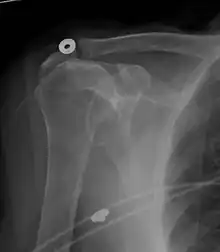

Diagnostic modalities, dependent on circumstances, include X-ray, MRI, MR arthrography, double-contrast arthrography, and ultrasound. Although MR arthrography is currently considered the gold standard, ultrasound may be most cost-effective.[31] Usually, a tear will be undetected by X-ray, although bone spurs, which can impinge upon the rotator cuff tendons, may be visible.[32] Such spurs suggest chronic severe rotator cuff disease. Double-contrast arthrography involves injecting contrast dye into the shoulder joint to detect leakage out of the injured rotator cuff[33] and its value is influenced by the experience of the operator. The most common diagnostic tool is magnetic resonance imaging (MRI), which can sometimes indicate the size of the tear, as well as its location within the tendon. Furthermore, MRI enables the detection or exclusion of complete rotator cuff tears with reasonable accuracy and is also suitable to diagnose other pathologies of the shoulder joint.[34]

MRI

Magnetic resonance imaging (MRI) and ultrasound[42] are comparable in efficacy and helpful in diagnosis although both have a false positive rate of 15 - 20%.[43] MRI can reliably detect most full-thickness tears although very small pinpoint tears may be missed. In such situations, an MRI combined with an injection of contrast material, an MR-arthrogram, may help to confirm the diagnosis. It should be realized that a normal MRI cannot fully rule out a small tear (a false negative) while partial-thickness tears are not as reliably detected.[44] While MRI is sensitive in identifying tendon degeneration (tendinopathy), it may not reliably distinguish between a degenerative tendon and a partially torn tendon. Again, magnetic resonance arthrography can improve the differentiation.[44] An overall sensitivity of 91% (9% false negative rate) has been reported indicating that magnetic resonance arthrography is reliable in the detection of partial-thickness rotator cuff tears.[44] However, its routine use is not advised, since it involves entering the joint with a needle with potential risk of infection. Consequently, the test is reserved for cases in which the diagnosis remains unclear.